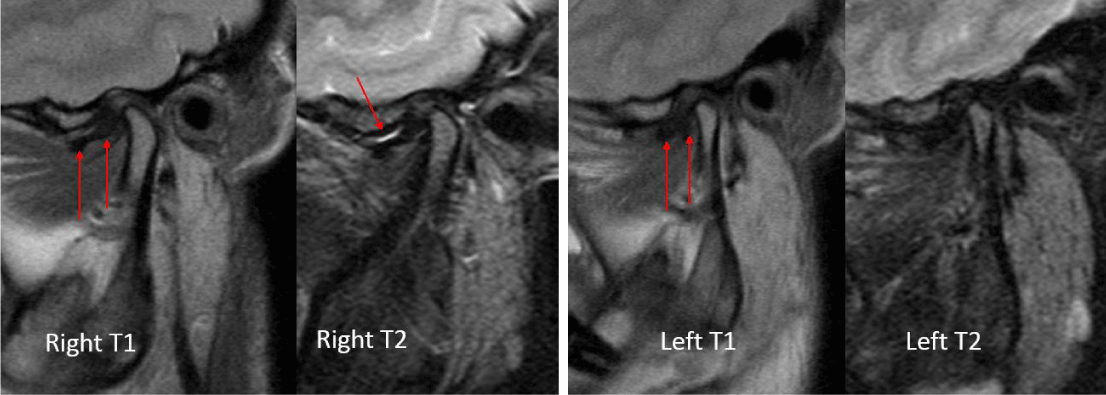

A 24-year-old female presented with a two-month history of right TMJ pain and locking. Examination revealed a 33mm mouth-opening with deviation to the right, bilateral mandibular condyles and right masseter tenderness to palpation, intact cranial nerves and no joint loading. There was no facial or preauricular swelling. The CT scan showed left greater than right condylar flattening with intact cortical outline and no osteolysis (Figure 1). The MRI showed bilaterally displaced discs with the left being deformed (Figure 2). The patient then underwent bilateral arthroscopy. Diagnostic arthroscopy on the left revealed synovial growth with striking reddish-orange discoloration. The disc was seemingly spared from the disease process (Figure 3,4). Synovectomy and debridement were completed. Histologic examination revealed PVNS (Figure 5). On her 10-month follow-up she reported significant improvement in pain and functional-limitation scores. She had a painless, symmetric 35mm mouth-opening with no joint tenderness or loading.